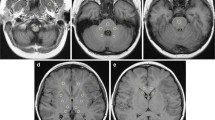

T1-weighted MPRAGE images (a, b) and T1 maps (c, d) at the level of the basal ganglia in a 12-year-old girl with status post cerebellar astrocytoma. An interval of 18 months and four administrations of gadobutrol elapsed between the time point (a, c) and the second time point (b, d). While the T1-weighted images do not indicate a difference (same windowing), a small decrease of the age-adjusted T1 time from − 6.0 to − 13.5 ms can be measured in the T1 maps of the putamen

The biexponential model was successful in age-adjusting T1 values with normally distributed residuals in the normal cohort. In linear mixed model analysis, there was a significant decrease of T1adj with the number of gadobutrol administrations in the GP (p = .012) and putamen (p = .03) (Table 2 and Fig. 3). There was neither a significant decrease in T1adj in the remaining brain regions nor a significant residual effect of age on T1adj in multiple linear regression (supplemental Figure 2). An additional effect on T1 values in the study cohort compared with the normative cohort not caused by age or number of gadobutrol administrations was observed in the GP, putamen, thalamus, and frontal white matter. The results of the linear mixed model were congruent to those obtained with the generalized additive mixed model (supplemental Table 2). The interobserver variability was excellent with an intraclass correlation coefficient greater than 0.96 in each brain region (supplemental Table 3). Figure 4 illustrates the T1 relaxation time raw data for the study and normative cohorts without age adjustments.